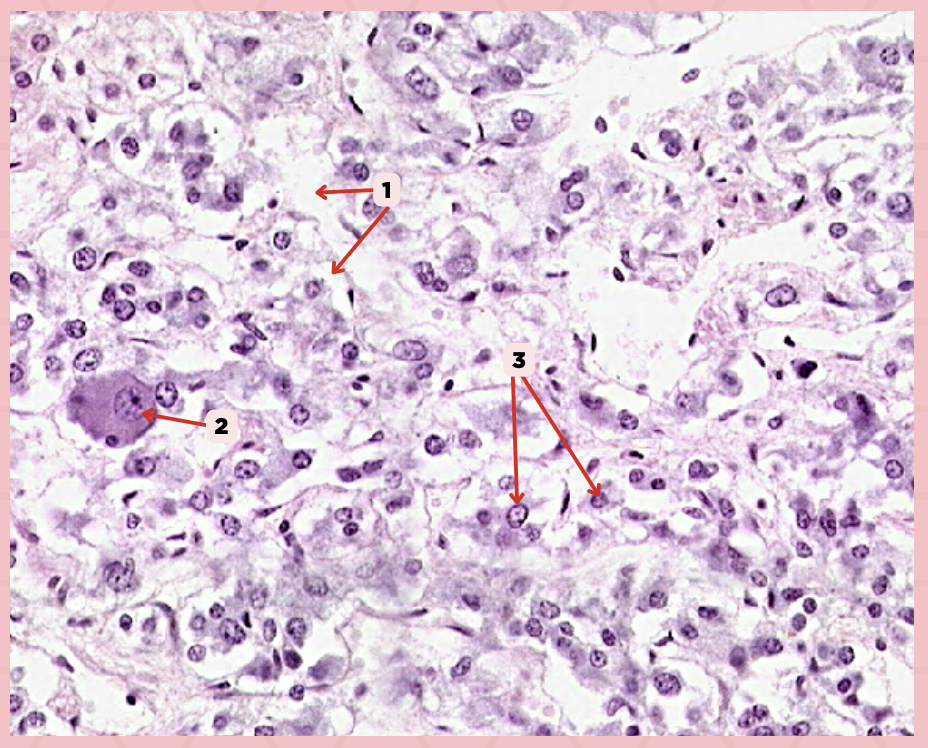

Pancreas

Identify the specimen.

Islets of Langerhans

Identify the structure labeled as 1.

Pancreatic Acini

Identify the structure labeled as 2.

Reticular Tissue

Identify the structure labeled as 3.

Beta-cells

Which cells occupy the central area of #1?

Pancreatic Acini

#3 delineates the pale- staining cells from the darker-staining cells. What do you call the darker-staining cells?